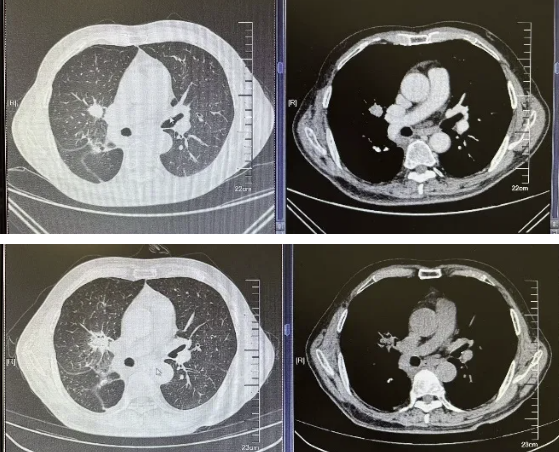

本次观摩学习了2例肺癌患者介入手术全程。第一例是79岁老年患者,该患者有肝癌,右侧肺鳞癌手术史,本次再发结节,不能再次手术,进行了磁导航支气管镜下机器人辅助活检及射频消融治疗。

第二例为81岁合并有肺纤维化的老年患者,由于肺功能较差,不能耐受手术,进行了磁导航下支气管镜肺活检以及冷冻消融。